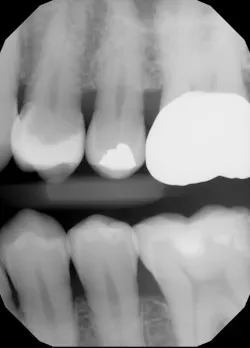

A 68-year-old patient presented with the upper right first premolar with occlusal amalgam and two distal marginal ridge fractures and discoloration under the mesial marginal ridge (figure 1). He previously had an extraction due to a fracture on his lower arch and wanted to treat the upper first premolar proactively. The existing occlusal amalgam was removed under rubber dam isolation. Caries were visualized clinically, and cracks were visualized with transillumination under both marginal ridges (figure 2). The premolar was prepared using a nonretentive cavity preparation design to allow the resin to flow in, out, and around the tooth (figure 3). Particle abrasion with 27 microns at 40 psi (PrepStart, Danville Products) was completed for microretention and biofilm removal before matrices, phosphoric acid etch (figure 4), and adhesive were placed.

Polymerization was completed in a three-point light-cure technique, curing from the occlusal, buccal, and lingual surfaces with and without separators and wedges present. Final contouring with discs and polishing brought the spectral highlights of the composite to a high luster (figures 6 and 7). Occlusal evaluation was completed along with a postoperative radiograph (figure 8). The patient reported no postoperative sensitivity.